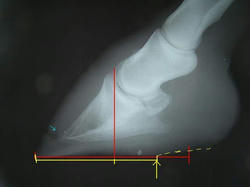

ヒールアップに関して、蹄壁と蹄底の角度を測ってくれました。

前回は65°。

パットをフラットなものにしたら62°。

3°の変化でも本人にとっては大きく変化したようで、だいぶ軽快に肢を運ぶようになりました。

見た目的にも前回の装蹄後よりも蹄の傾きが緩やかになり、私もホッとしました。

次回からは削蹄で少しずつ角度を寝かせていくそうです。